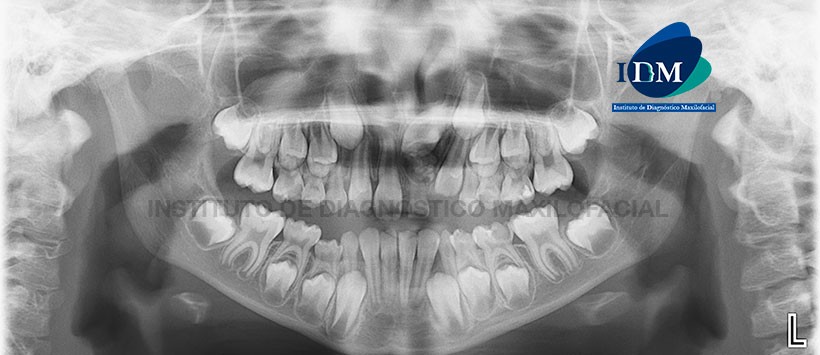

Paciente femenino de 07 años de edad, es referido al Instituto de Diagnóstico Maxilofacial – IDM para examen tomográfico por cirugía de odontoma.

A la evaluación de la radiografía panorámica (Figura 1) una imagen radiopaca de densidad dentaria delimitada con un halo radiolúcido que ocasiona la impactación de la pieza 21.